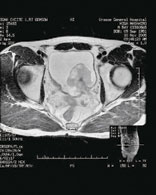

図2

図3

54 歳男性で1 年前から血尿あるも放置してい た。図2 は治療前のMRI で膀胱左側に基部の広 い大きな非乳頭状腫瘍で表面石灰化していた。 Complete TUR 後に動注療法34 回、2 年間施 行する。図3 は治療後のMRI で再発なく、遠隔 転移も認めない。治療開始後4 年目である。